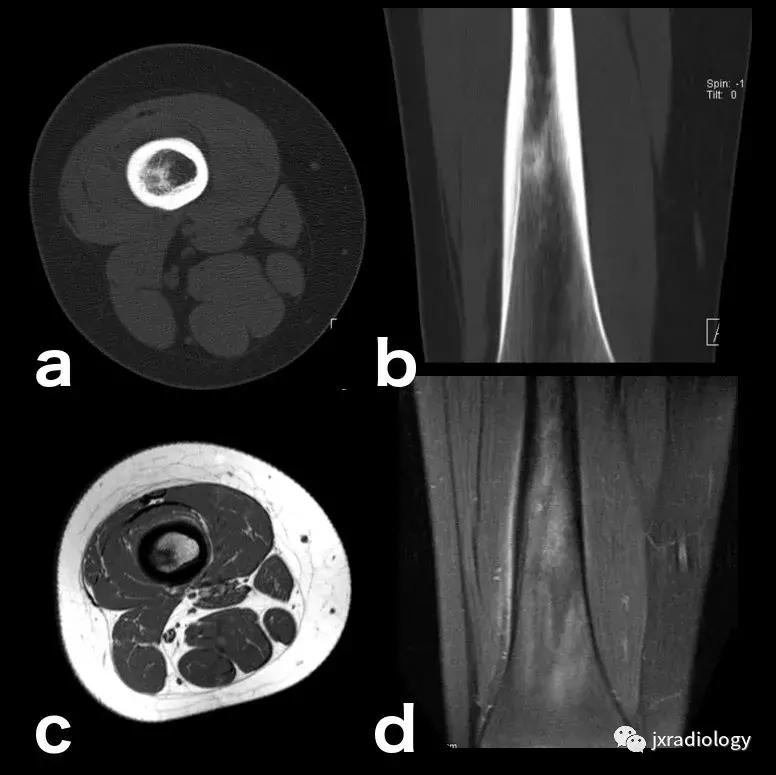

图20:患有血红蛋白病的患者(例如镰状细胞性贫血),在这种情况下,容易发生继发于毛细血管阻塞的骨坏死。这种阻塞导致毛细血管静水压升高,造成水敏性序列中低信号骨梗死周围的高信号水肿。这是充血性骨髓水肿的一个例子(由于骨髓空间毛细血管床液体流出受损)。该患者还表现出广泛的红骨髓转化,如T1-WI中的骨髓信号所示(远低于周围脂肪组织并略高于肌肉组织)和DP-FS-WI(未完全饱和,保持略高信号)( a:冠状面DP-FS-WI; b:冠状面T1-WI; c:轴向T1-WI; d:矢状面DP-FS-WI)。